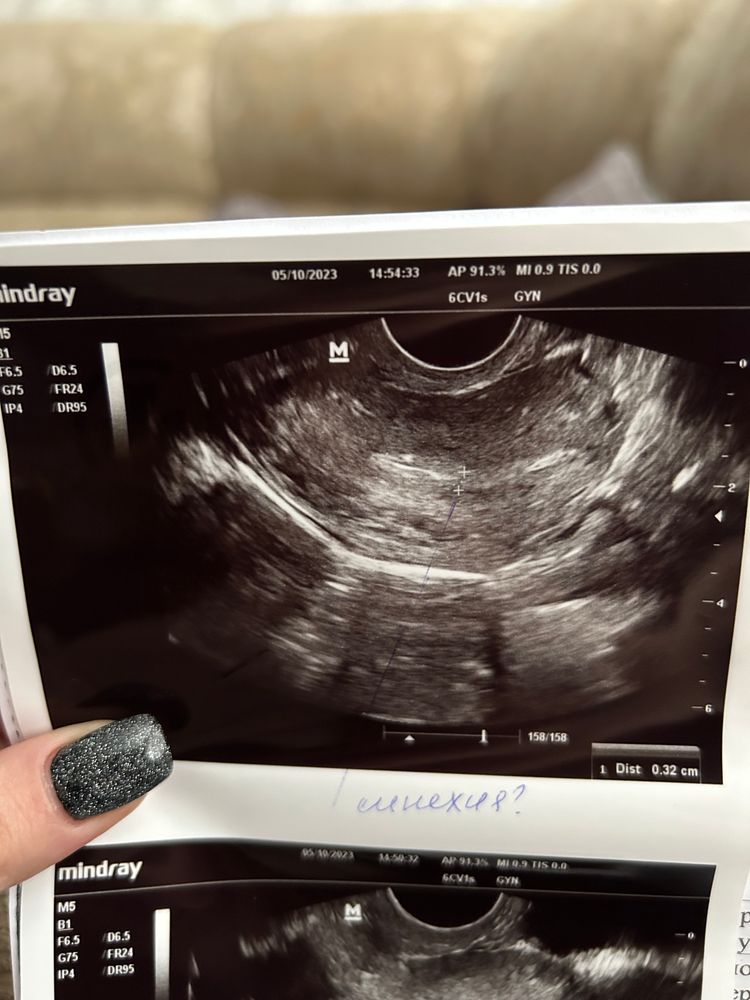

Синехия? Фото узи прилагаю

Ходила сегодня на фолликулометрию, и обнаружили вот это. Врач сказала, что это либо резец от давней чистки, ибо была ЗБ (синехия), либо так выглядит моя матка и предположила, что она седловидная. У кого такое было? Поделитесь

У меня синехия выглядела так.

Было ощущение, что полоска смыкания эндометрия прерывается и потом опять появляется.